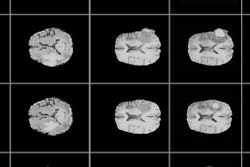

Canon will use Nvidia's DGX platform of servers and workstations based on GPU technology to process large volumes of medical data generated by Abierto VNA, a medical data management system that Canon launched in January.

The collaboration will combine Nvidia's specially optimized AI software with Canon's graphical user interface to support the design, deployment, and operation of advanced deep-learning algorithms in healthcare. The companies believe the collaboration will help in the development of optimized healthcare delivery systems to support early detection and assisted diagnosis.